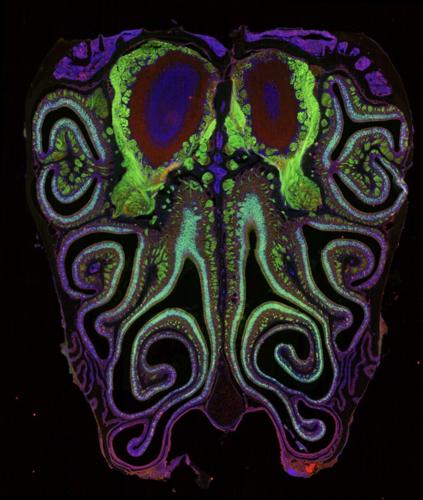

A microscope photo of a cross section of a mouse nose. The mouse was genetically modified to express green fluorescent protein in smell neurons. A small subset of dying neurons is labeled in red. (Datta Lab via SWNS)

kAm(@C<:?8 :? >:46[ DEF5J D6?:@C 2FE9@C s2EE2 2?5 9:D E62> 92G6 ?@H 4C62E65 E96 7:CDE 56E2:=65 >2A @7 9@H E96 E9@FD2?5\A=FD EJA6D @7 D>6== C646AE@CD :? E96 ?@D6 2C6 @C82?:K65]k^Am

kAm%96J 5:D4@G6C65 E92E F?=:<6 H92E C6D62C496CD 925 AC6G:@FD=J 36=:6G65[ E96 ?6FC@?D 6IAC6DD:?8 E96 C646AE@CD 92G6 2 9:89 568C66 @7 DA2E:2= @C82?:K2E:@?i E96J 7@C> 9@C:K@?E2= DEC:A6D 32D65 @? C646AE@C EJA6 7C@> E96 E@A @7 E96 ?@D6 E@ E96 3@EE@>]k^Am

kAm%96 E62> 5:D4@G6C65 E92E E96 ?6FC@?D 2C6 @C82?:K65 :?E@ E:89E[ @G6C=2AA:?8[ 9@C:K@?E2= DEC:A6D 7C@> E96 E@A @7 E96 ?@D6 E@ E96 3@EE@> 32D65 @? E96 EJA6 @7 D>6== C646AE@C E96J 6IAC6DD]k^Am

kAm%96J D2:5 E96 9:89=J @C82?:K65 C646AE@C >2A H2D 4@?D:DE6?E 24C@DD E96 >:46 2?5 >:CC@C65 E96 @C82?:K2E:@? @7 D>6== >2AD :? E96 3C2:?[ ;FDE =:<6 C6D62C496CD 92G6 @3D6CG65 :? G:D:@?[ 962C:?8[ 2?5 E@F49]k^Am